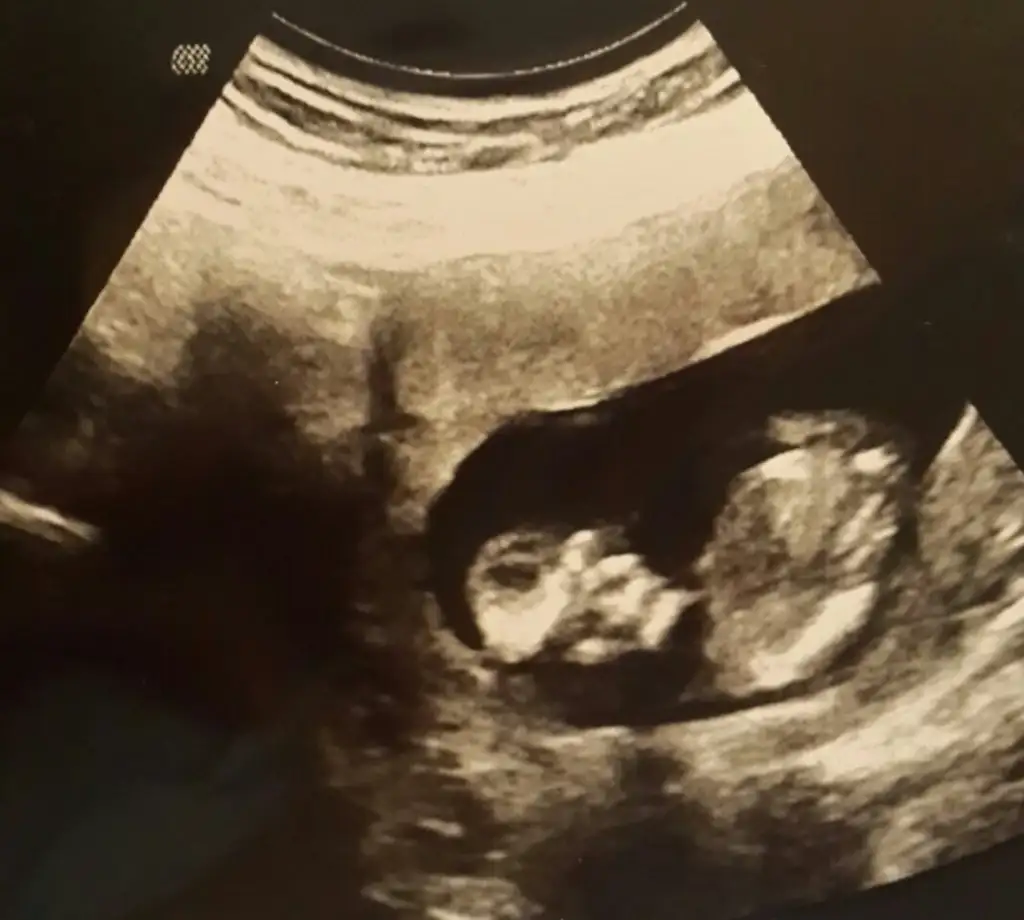

dr soylemeden siz gorun genital nub teorisi ( bebegin cinsiyeti)

Bu bebiste kardeşim in tahmin de bulunabilir misiniz